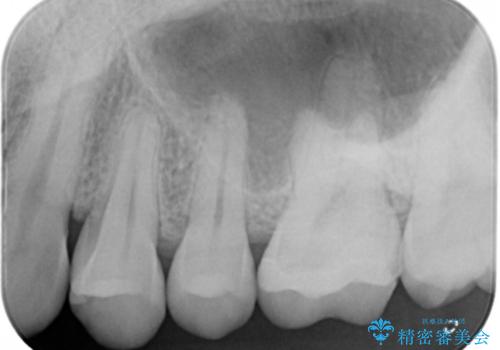

- 左上6番の銀歯のやり変えを希望し来院された患者様です。

切削量・形態を考慮し、セラミックインレーでの治療を計画しました。

銀歯直下のう蝕が深かったのでCRで裏層した上で形成、印象をしています。